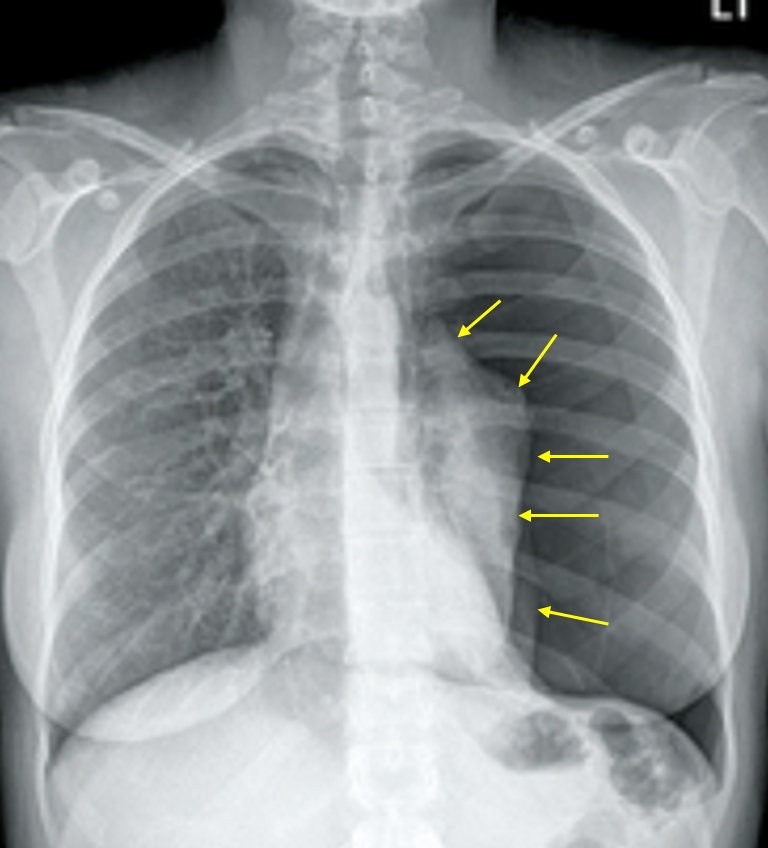

Img | CXR: Lt. lung total collapse, loss of Lt. pulmonary vascularity |

• CXR에서 좌측 폐의 total collapse, 좌측 폐혈관 음영이 사라진 소견이 있으므로 기흉으로 진단한다. 환자가 젋고 특이 병력이 없으므로 PSP가 의심된다. 한편 심전도에 특별한 이상은 없는 것으로 보인다.

• V/S은 비교적 안정적이며 흉통/호흡곤란 등 증상이 얼마나 심한지 구체적으로 지문에 제시되지는 않았다. 추적 관찰 및 산소 공급을 고려할 수도 있겠으나, 한쪽 폐가 total collapse될 정도로 기흉의 크기가 매우 크기 때문에 흉관 삽입을 통해 경과를 관찰하는 것이 보기 중에서는 가장 적절한 치료라고 볼 수 있다. 또한 산소 치료는 흉관 삽입 여부와 관계없이 기흉의 흡수를 돕기 위해 고려할 수 있다.